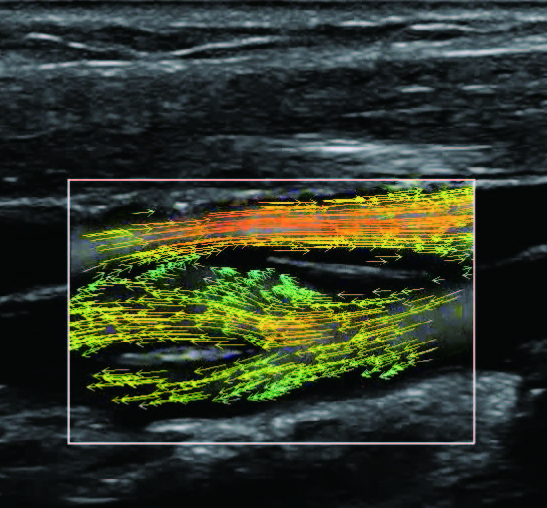

На изображениях, приведенных ниже показаны примеры из клинической практики врачей ультразвуковой диагностики, полученные в процессе апробирования прибора Mindray Resona 7. Приводится наглядные примеры сравнения традиционного режима ЦДК и режима V Flow (Vector Flow).

Изображена яремная вена и бифуркация сонной артерии. CAA, ICA и ECA показаны на одном изображении. В режиме ЦДК отсутствует подробная гемодинамика. В режиме V Flow отображаются данные о скорости и направлении движения частиц крови во всей зоны интереса, включая изменения характеристик кровотока в сонной артерии и яремной вене.